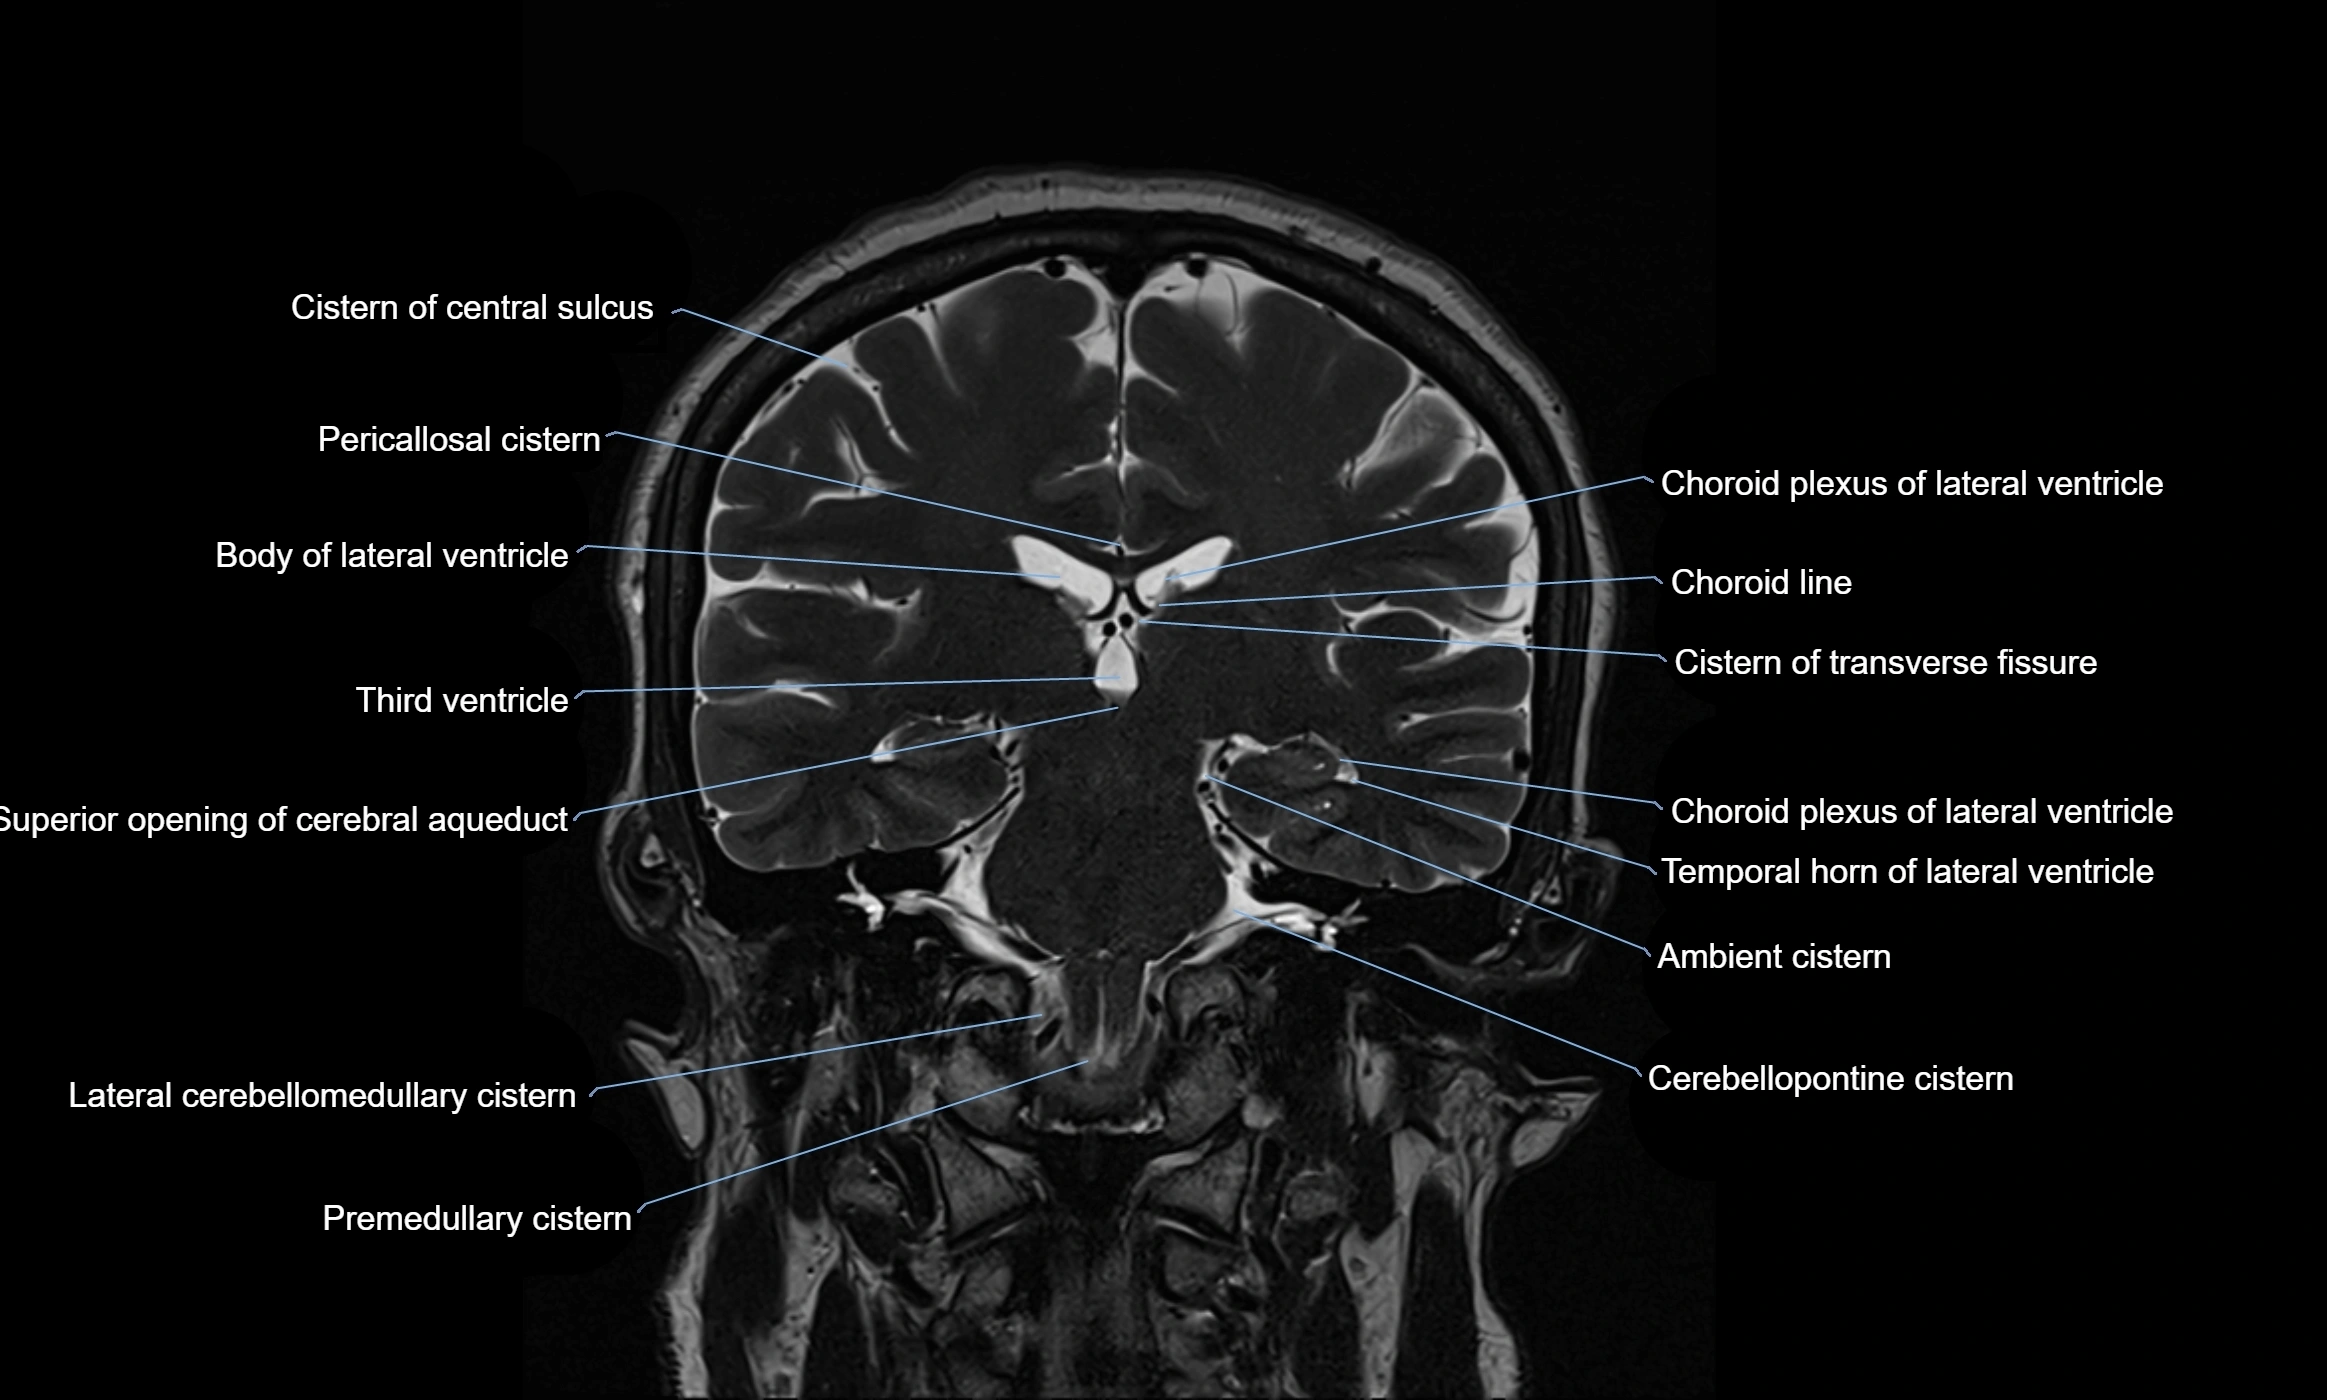

The ambient cistern is a paired, narrow, and elongated subarachnoid space located bilaterally along the lateral aspect of the midbrain. It serves as a conduit between the interpeduncular cistern anteriorly and the quadrigeminal cistern posteriorly. This cistern houses critical neurovascular structures, including parts of the posterior cerebral artery, superior cerebellar artery, trochlear nerve (cranial nerve IV), and the basal vein of Rosenthal. It plays an important role in the circulation of cerebrospinal fluid (CSF) and provides an anatomical corridor for various vessels and nerves passing around the midbrain.

MRI Appearance

• T2-weighted images:

• The cistern is hyperintense (bright) due to the high water content of CSF.

• Encapsulated vessels and nerves are seen as flow voids or hypointense lines within the bright background.